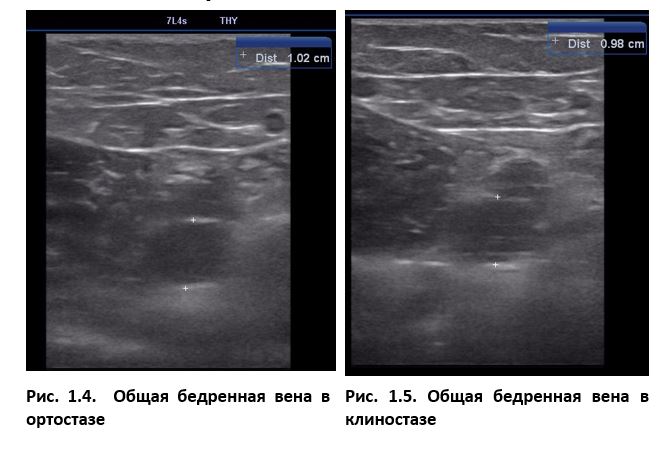

Ультразвуковое исследование вен нижних конечностей мы всегда проводим в положении больного стоя (ортостаз). Только так возникает достаточное ортостатическое давление на венозные клапаны, которое вызовет рефлюкс в случае их несостоятельности. Одновременно, варикозно расширенные вены лучше визуализируются в этом положении, а их подкожное расположение позволяет в комплексе с ультразвуковой картиной правильно оценить распространение патологии. Так же, в положении стоя мы проводим ультразвуковое исследование глубоких вен при подозрении на тромбоз. Проблема в том, что когда пациент ложится, вена в поперечном сечении из круга превращается в эллипс. Тромб, если он есть в просвете вены, зажимается между ее стенками и врачу может показаться, что он прикреплен, т. е. не флотирует. В итоге в положении лежа (клиностаз) ошибочно диагностируется окклюзивный тромбоз. Если же больного попросить встать, вена в поперечном сечении вернется к округлой форме и вполне может оказаться, что у него тромбоз флотирующий и эмболоопасный. Проба Вальсальвы, выполненная при этом, дополнительно поможет установить, что длина флотирующей головки намного больше, чем казалось в неподвижном ортостазе.